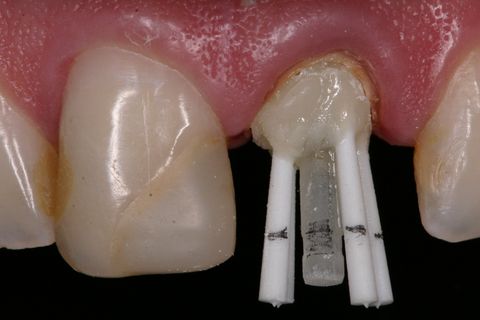

Pino de fibra de vidro #3 (Exacto) pinos acessórios (Reforpin) Angelus, Brasil

Inicialmente, foi removido o tecido cariado do remanescente dental e realizado a seleção do pino de fibra de vidro (Exacto # 3, Angelus, Brasil) e também foram selecionados pinos acessórios (Reforpin, Angelus, Brasil) (Figuras 4).

Isolou-se o conduto radicular com óleo mineral e inseriu-se a resina composta (Fill Magic NT Premium, Coltene-Vigodent, Brasil) sobre o remanescente dentário com auxílio de uma espátula suprafill #1/2 (Figuras 5 e 6). Após o preenchimento do conduto com resina, foi inserido o pino Exacto cônico e os pinos acessórios previamente silanizados (Silano, Angelus, Brasil) e com a aplicação do adesivo (Fusion Duralink, Angelus, Brasil) (Figuras 7, 8 e 9). Em seguida, promoveu-se a fotoativação inicial do conjunto pino-resina por 20 segundos.